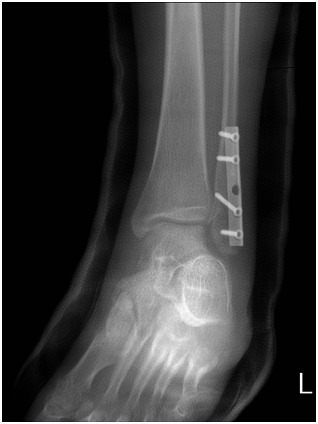

그리고 현재 철심 제거수술을 받을 예정입니다.

1. 의사소견: 다 붙었기 때문에 이제 철심제거가 가능함. 만약 불안하다면 6개월 뒤에 수술해도 된다고 합니다.

하지만 저는 아직 시리고저리고 아픈데.. x-ray상 제거해도 될까요?

현재]